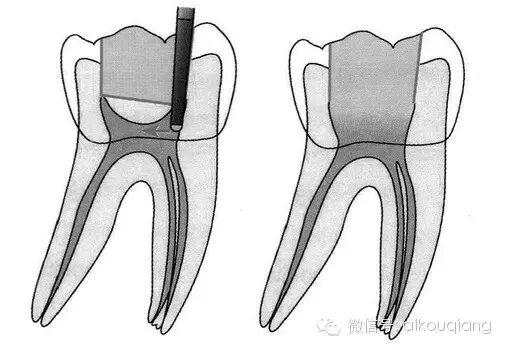

“G型扩孔钻预备:应用GG钻预备根管冠2/3可获得良好的根管冠部通道。GG钻进人根管前,一定要用10#或l5#根管锉探查和通畅根管,如果GG钻1#进入根管有困难时,应初步预备根管,再使用GG钻进入。一般来说,GGl#进入根管l6~17mm;GG2#,GG3#后退2~3mm;GG4#进入根管口下2~3mm;GG5#,GG6#仅作根管口以上部分预备,便于髓腔与根管口形成直线通道。GG钻勿进入根管的深部,避免过度去除牙本质,造成根管壁的薄弱,形成穿孔或瓶颈样预备(见下图)

口腔H锉怎么消毒根管治疗器械的选择_https://www.jmylbn.com_新闻资讯_第22张

图 根管的瓶颈样预备(右图)